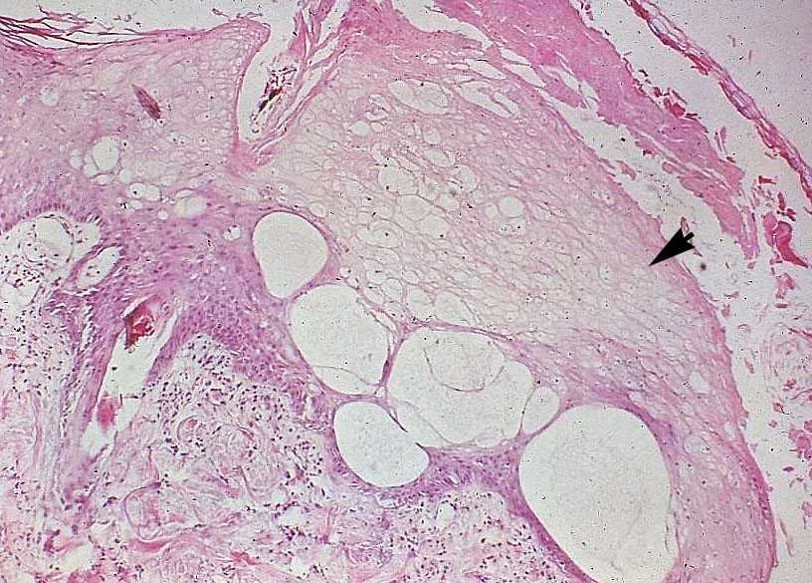

What is seen here demarcated by the black arrow? Red arrows?

Ballooning degeneration (black arrow);

Skin pale and swollen, filled with water, starts to swell and eventually forms large vesicles (red arrows)